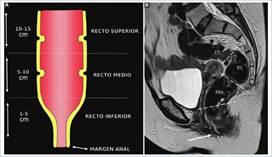

Histológicamente, el recto está compuesto por tres capas concéntricas, siendo de interno a externo: la mucosa, la submucosa y la muscular propia. Por fuera de esta última se encuentra un componente adiposo: el mesorrecto, el cual está limitado externamente por la fascia mesorrectal (FMR), que se evidencia como una delgada línea hipointensa en secuencias potenciadas en T23 (Fig. 1).

Se debe determinar con certeza si la lesión se encuentra a nivel rectal o en el colon sigmoides, ya que en ambos casos existe un abordaje quirúrgico distinto3. Uno de los métodos más utilizados por las guías internacionales para la definición de tumor de recto es la medición de la distancia entre la porción distal de este y el margen anal, considerando a todos aquellos tumores ubicados a una distancia ≤ 15 cm del margen anal como tumor rectal. A su vez, se los subclasifica en tumores de recto superior, medio y/o inferior (Fig. 2)3),(4),(5. El recto es un órgano con una porción intraperitoneal y otra extraperitoneal, que pueden ser diferenciadas mediante la identificación de una fina membrana hipointensa en T2 correspondiente a la reflexión peritoneal anterior. Esta suele visualizarse en el plano sagital y une las vesículas seminales en el hombre y el fondo de saco de Douglas en la mujer, con la cara anterior del recto medio (Fig. 3)3,6. Por encima de esta, el peritoneo recubre las caras anterior y lateral del recto superior y la cara anterior del recto medio, mientras que el recto inferior es completamente extraperitoneal6. A su vez, la FMR rodea completamente al mesorrecto por debajo de la reflexión peritoneal y por su caras laterales y posteriores por encima de esta3 (Fig. 4).